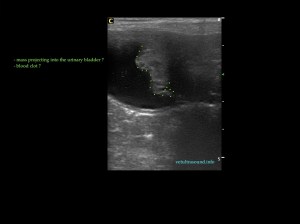

Τα πήγματα αίματος πολλές φορές μπορεί να προσομοιάζουν μάζες της ουροδόχου κύστης, ειδικά αν δεν είναι αρκετά γεμάτη ή δεν έχουν σχηματιστεί πρόσφατα. Σε αυτή την περίπτωση περιμένουμε να γεμίσει ώστε να εξετάσουμε:

– αν έχει αιμάτωση η μάζα που εντοπίσαμε

– αν προσφύεται στο βλεννογόνο

– αν μετά από αλλαγή θέσης του ασθενή μετακινείται

Blood clots can resemble masses, especially when the urinary bladder is not fully distended or the clot was not recently formed.

Tips for differentiating a blood clot from a mass (when cytology results are not well defined):

– Evaluation of blood flow in the mass with colour/power Doppler

– The mass should invade the mucosa (if we can see the mucosa enclosing the neck of the mass)

– Changing the patient’s position may reveal that this ‘’mass’’ is not attached to the bladder wall

– Revaluate the patient the next day (the clot may have gone away) or allow the patient to go for a walk and revaluate.